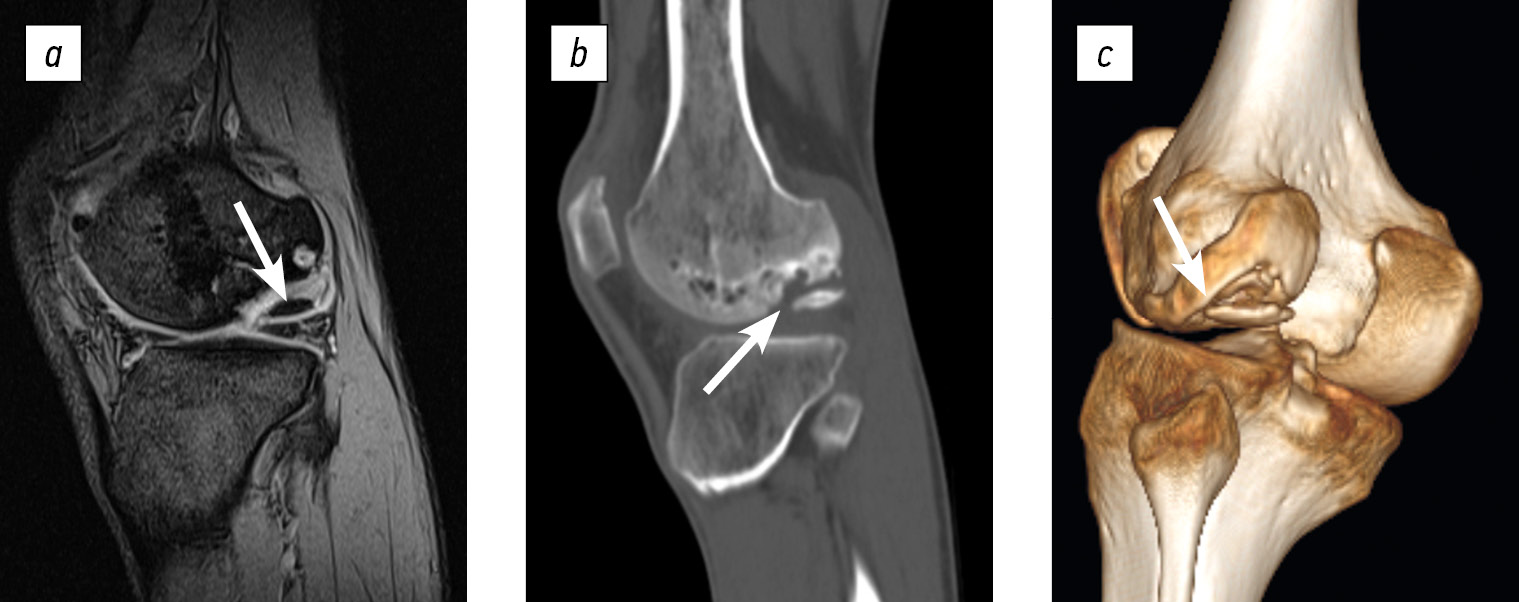

Radiographic evaluations—including X-ray, spiral computed tomography, and magnetic resonance imaging—identified an osteochondral defect in the central region of the medial femoral condyle, measuring 2.0 × 1.4 × 1.0 cm. The lesion was classified as a deep defect (ICRS grade IV). Postoperative changes were recorded, accompanied by synovitis of the right knee joint and early signs of secondary deforming osteoarthritis (stages I–II) (Fig. 1).

Fig. 1. Diagnostic imaging of patient B (age: 17 years at admission): a, X-ray of the right knee joint in anteroposterior and axial views; b, computed tomography scans exhibiting frontal, sagittal, and axial slices through the lesion; c, magnetic resonance imaging scans, frontal and sagittal views through the lesion. The area of destruction is indicated by an arrow.